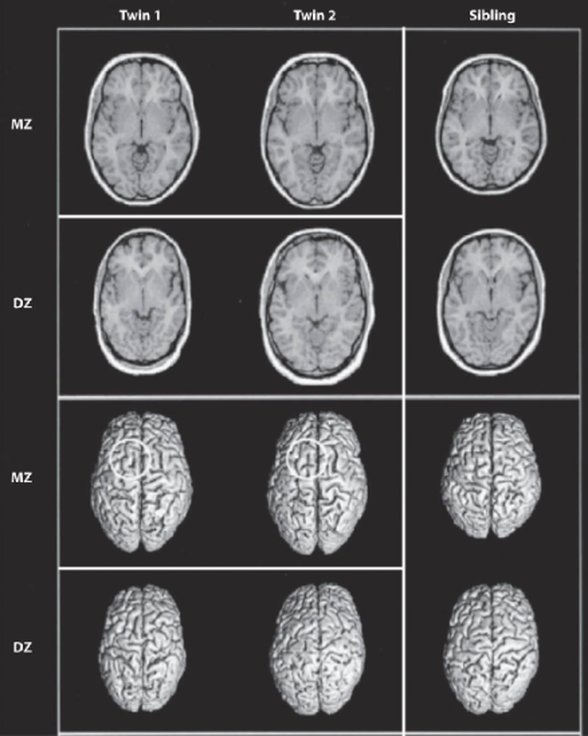

Bu sorunun cevabı bir insanın kişilik özelliklerinin ve karakterinin ne derecede kalıtsal ve gelişimsel (developmental) olduğuna ve çevresel etkenlerin belirlenmesinde özgür iradenin ne derecede bir etken olduğuna bağlı. Değiştirilebildiğinin aksine değiştirilemeyeceği doğrultusunda davranışsal genetik ve psikometri alanlarından bir çok kanıt gösterilebilir. Özellikle de son otuz yıl içinde gen mi çevre mi (nature vs nurture) tartışmasında genlerin insan davranışında, psikolojisinde ve zeka kapasitesinde etkisini defalarca kanıtlar nitelikte çalışmalar yürütüldü. Bu çalışmalar arasında en önemlilerinden birisi de Thomas J. Bouchard tarafından 1979 yılında başlatılan ve sonuçları 1990 yılında yayımlanan Minnesota İkiz Çalışması idi. Bu çalışma, yüzden fazla birbirlerinden ayrı büyütülmüş tek yumurta (monozygotic) ikizlerinin kişilik özelliklerinin, sosyal tavırlarının ve hobilerinin birbirleriyle aynı ortamda büyütülmüş tek yumurta ikizlerinden farklı olmadığını ortaya koymuştur (Bouchard 1990). Buna ek olarak Bouchard bilimsel literatürde kendi çalışmasını takiben biriken yığınlarca kanıdı harmanlamak ve özetlemek amacıyla 2004 yılında bir kağıt daha yayımlamıştır. Bu makalesinde ise de Beş Büyük faktör kuramının bileşenleri olan karakter özelliklerinin ortalama 50% kalıtsal olduğunu ortaya koymuştur (Bouchard 2004). Buna ek olarak Rutter da benzer bir şekilde biriken literatürü gözden geçirme niteliğinde olan kağıdında "genetik faktörlerin tüm normal ve abnormal psikolojik özelliklerde bireyler arasındaki farkın önemli bir kısmını oluşturduğunu" ve bunun "70%'ten fazla" olduğunu öne sürmüştür (Rutter 2002). Bu konuda en güncel verilerle de en kapsamlı eseri yaratan ve bu alana kendisi de göz ardı edilemeyecek büyük katkılarda bulunan Robert Plomin'dir ve yazdığı eserin ismi de Blueprint idir. Bunun üstüne de nörobilimci Kevin J. Mitchell beynin yapısında gelişimsel süreç sırasında ortaya çıkan farklılıkların davranışsal ve psikolojik açıdan ne tür farklılıklara yol açabileceğini kapsamlı bir şekilde açıkladığı Innate isimli eserinde çevresel etkenlerin etkisini daha da daraltan kanıtlar ortaya sürmüştür.